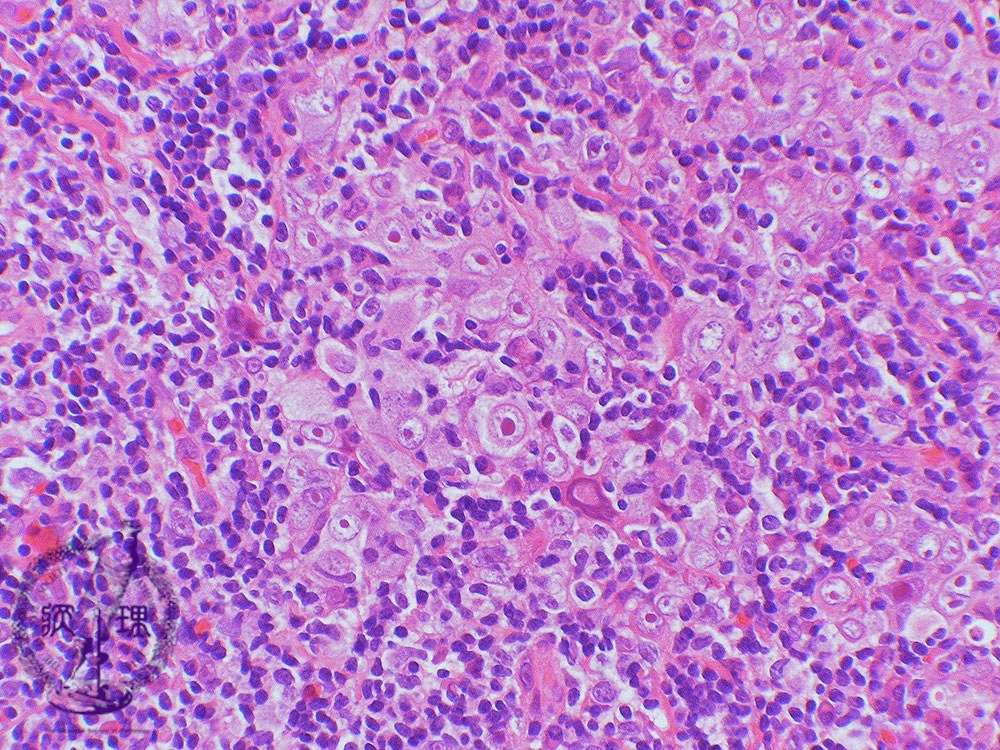

- ★(4)Nasopharyngeal carcinoma (lymphoepithelioma)

Microscopic view (high power view): Nasopharyngeal undifferentiated carcinoma is characterized by round to oval vesicular nuclei with large central nucleoli (arrow). Such undifferentiated carcinoma may arise in the middle pharynx, salivary glands, stomach and or thymus.